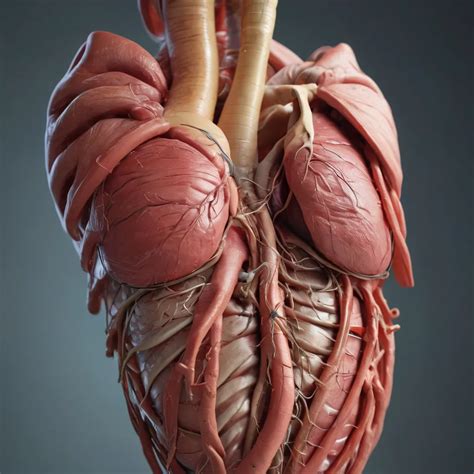

Medical Conditions